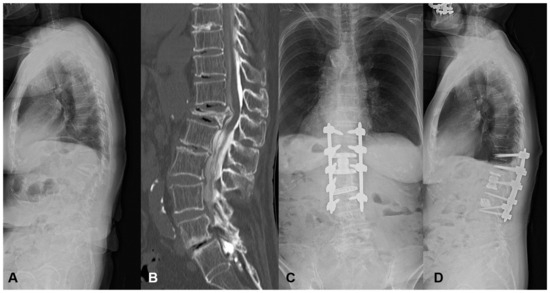

3.1.1. Case 1: 84 Years Old, Female, L1 Vertebral Collapse

She revealed severe motor weakness of right quadriceps, drop foot, and gait disturbance preoperatively. The L1 MIS corpectomy, artificial body replacement, and L2/3 XLIF were performed followed by PPS fixation. The local kyphosis of 24 degrees was corrected to 0 degrees postoperatively. Even with a high PI of 66 degrees, no mechanical complication occurred with the enhancement of the fixation level (Figure 4). The patient became ambulatory with the recovery of motor weakness.

Figure 4.

An 84-year-old female suffering from L1 vertebral collapse. The L1 MIS corpectomy, artificial body replacement, and L2/3 XLIF were performed followed by PPS fixation. The patient became ambulatory, and motor weakness recovered without mechanical complications. (A) Preoperative lateral X-ray, (B) Preoperative myelogram CT, (C) Standing AP X-ray at one year postoperatively, (D) Standing lateral X-ray at one year postoperatively.

This case was a typical example of thoracolumbar OVF with preoperative high mismatch. When the short-segment fusion was conducted, there was a very high risk for MC such as DJK.